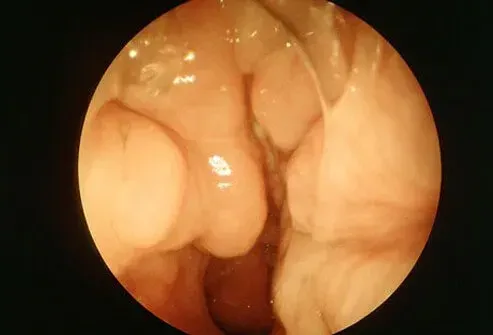

Polypes nasaux

Les polypes nasaux sont une prolifération de tissu dans les sinus qui peuvent bloquer l'écoulement du mucus et de l'air.